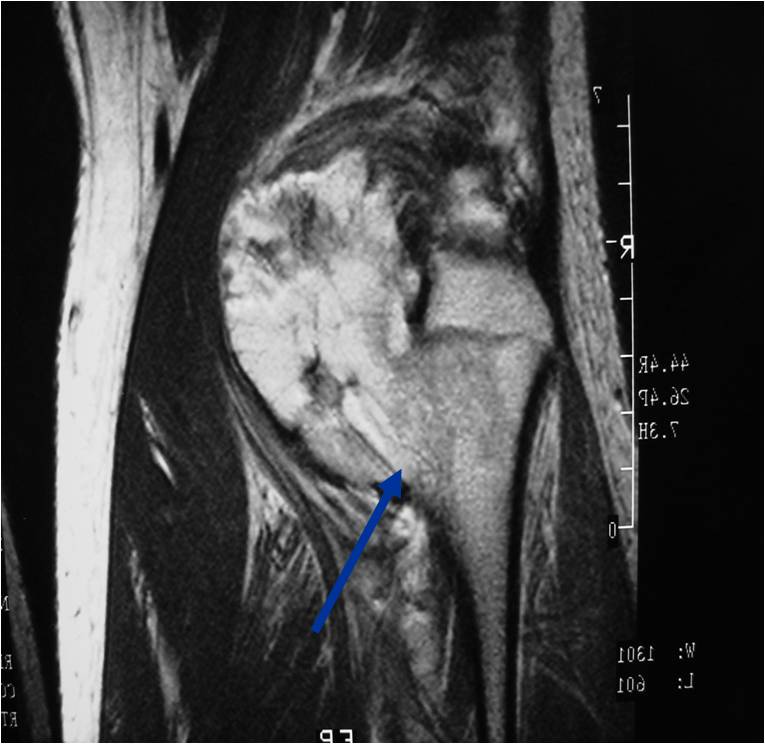

- Best test for evaluating thickness of cap and surrounding bursa

- Intermediate T1W Images

- High Intensity T2W Images because of fluid content

MRI: Secondary Chondrosarcoma of Proximal Femur: Thick Cartilage Cap (>2cm)